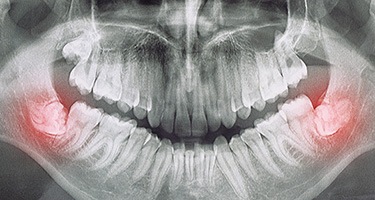

When the wisdom teeth become stuck, or impacted, this can create a variety of unpleasant symptoms, including pain towards the back of the mouth, shifting teeth, a flap in the gums that traps food, and even an infection. Typically, the best way to stop these issues and prevent others from developing in the future is to simply remove these teeth. The procedure usually takes just one or two appointments depending on the number of teeth, and the recovery time is often less than a week.

The very first step is always the same: numbing your mouth. That way, you don’t feel any pain during your time in the treatment chair. Once you’re ready to begin, our talented and experienced emergency dentist will gently grip the tooth, rock it loose, and extract it. Unless, of course, the wisdom tooth that needs to be removed is trapped underneath your gumline. In that case, Dr. Oshins will need to make an incision in your gums first to access it. Then, he will remove it piece by piece, helping to preserve your jawbone in the process.